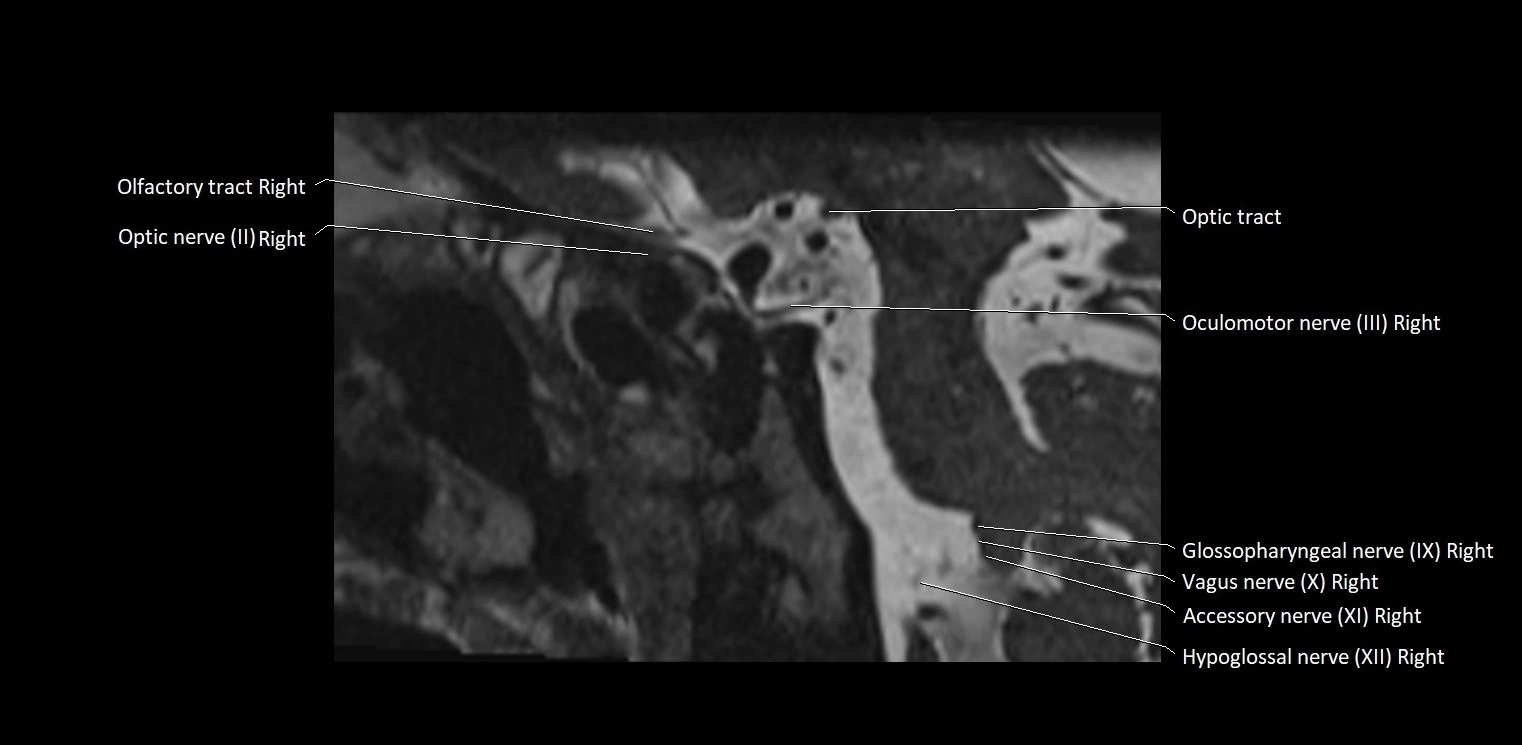

MRI Appearance

• The abducens nerve is a small, thin, linear structure

• Best visualized on high-resolution T2-weighted 3D MRI sequences (e.g., FIESTA or CISS)

• Seen as a hypointense (dark) line running from the brainstem at the pontomedullary junction, traversing the prepontine cistern, and entering Dorello’s canal under the petrosphenoidal ligament, then into the cavernous sinus, and finally the orbit

• May be challenging to visualize in standard MRI due to its small size

• Pathology may be inferred by absence, displacement, or enhancement of the nerve

MRI images

image